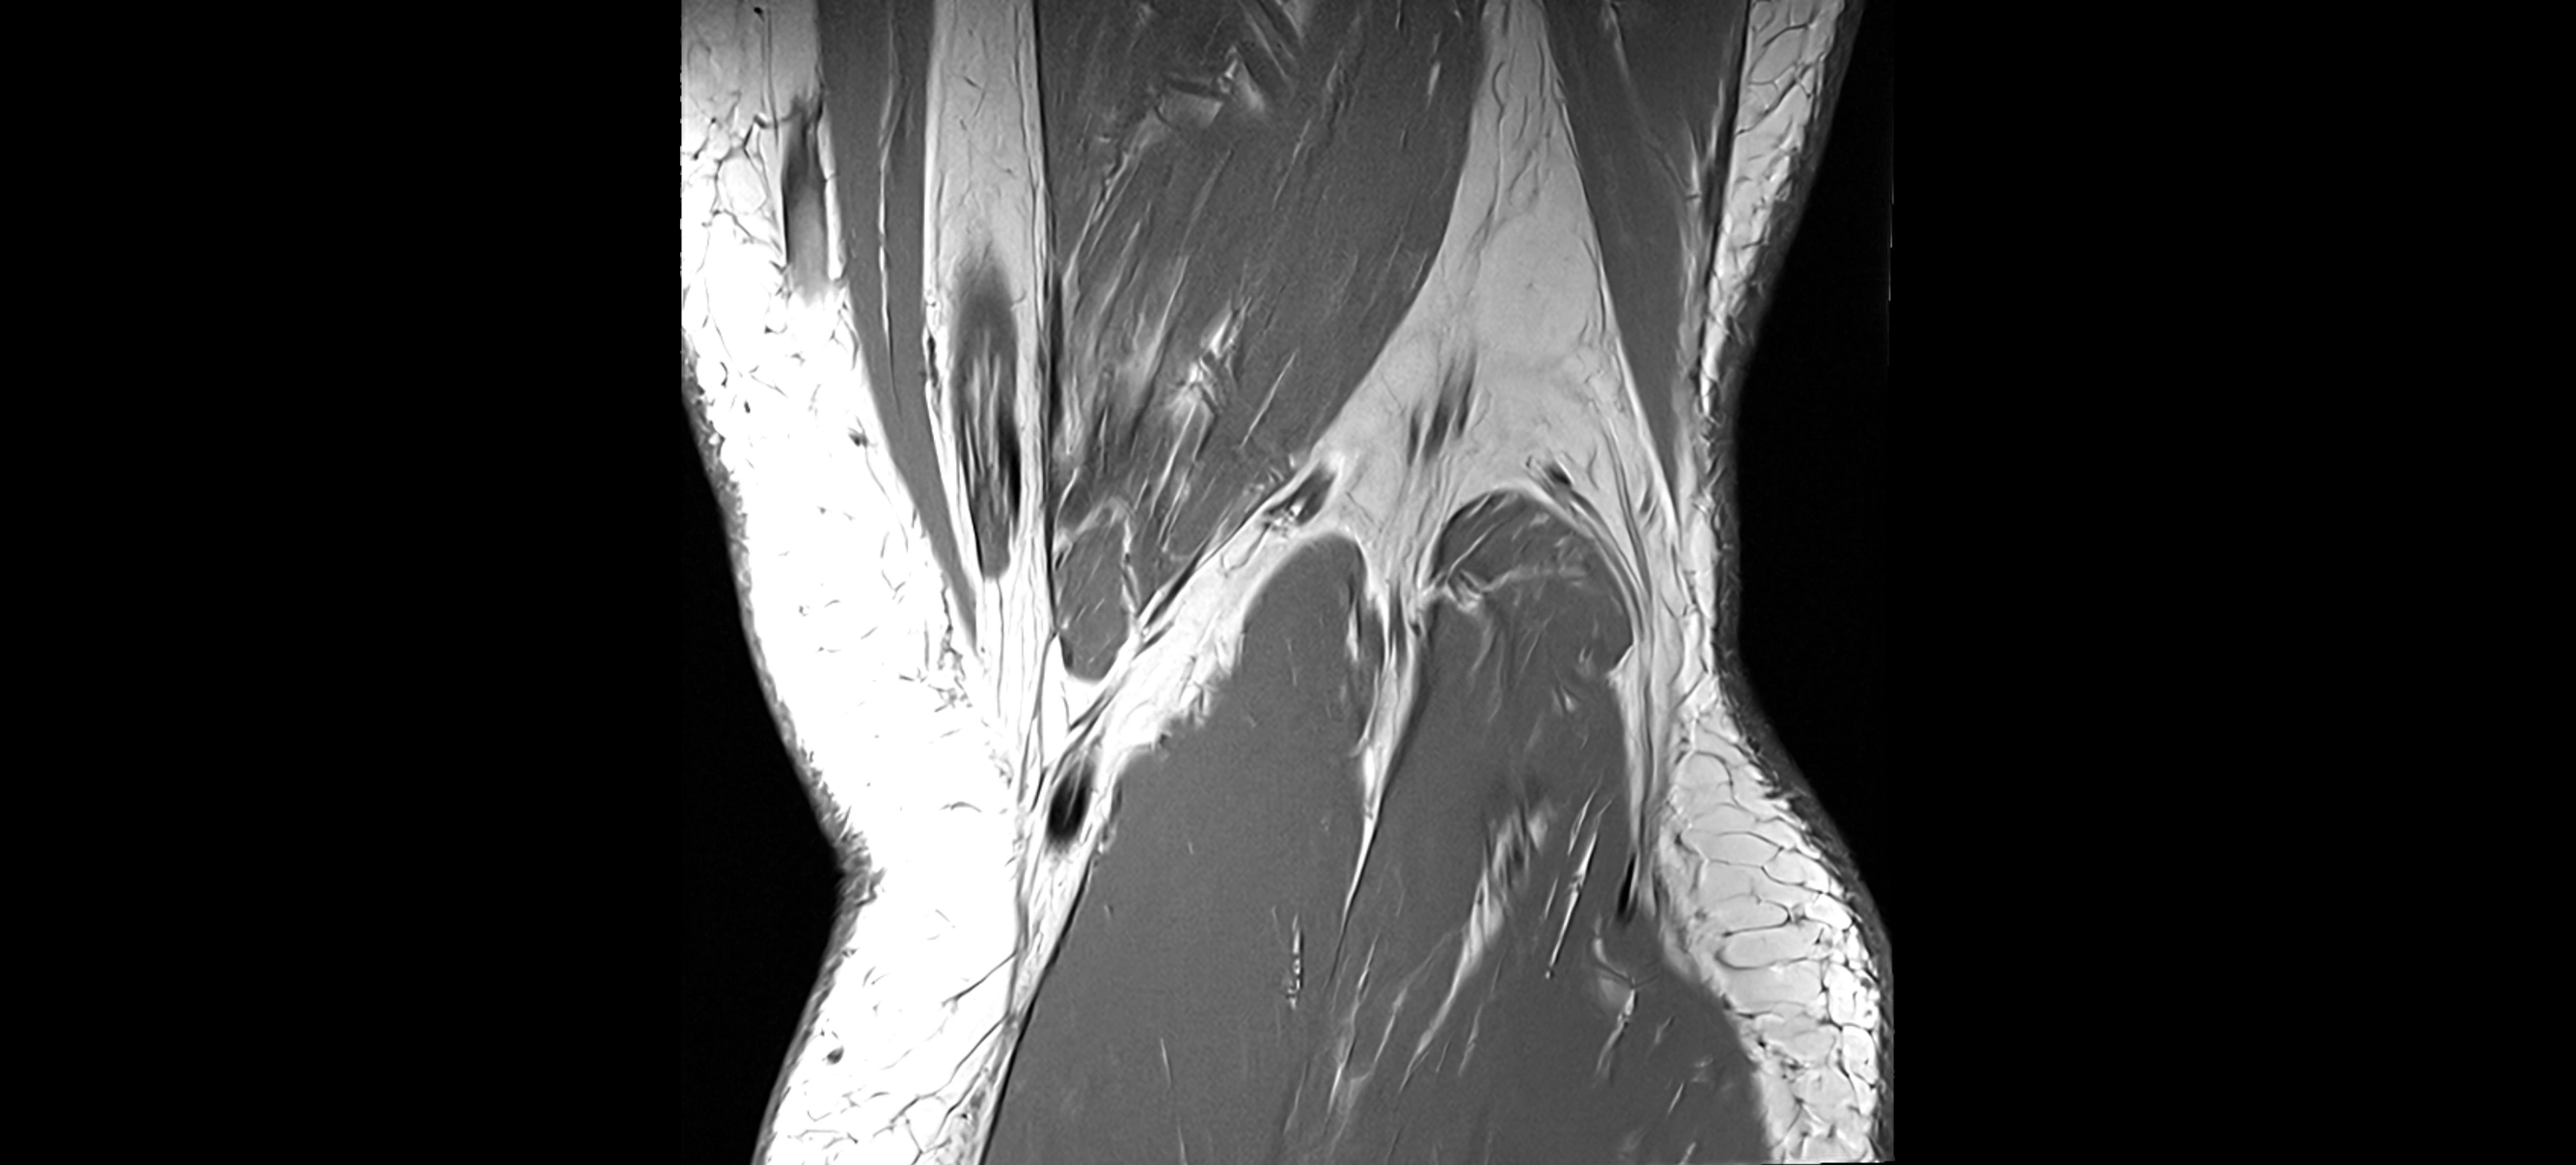

MRI images

image